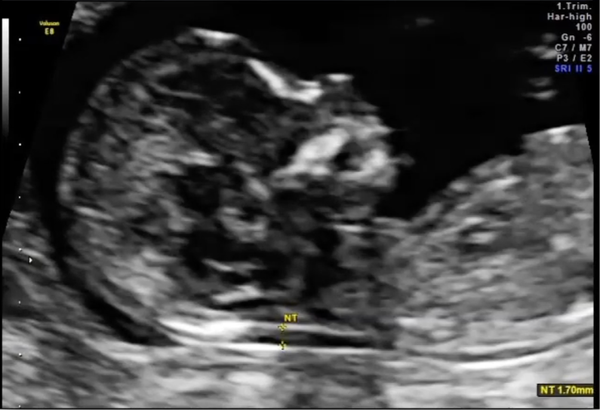

09:40 - 10:10 Ecografie 5-10 săptămâni - Asist. Univ. Dr. Cristina Ormindean

10:10 - 10:40 Screening de trimestru I – Dublu test / NIPT - Dr. Vlad Ormindean

10:40 - 11:10 Morfologia de trimestru I – ecografie 16-18 săptămâni - Prof. Dr. Răzvan Ciortea

Ecografie 5–10 săptămâni

Screening de trimestru I – Dublu test / NIPT

Morfologia de trimestru I – ecografie 16–18 săptămâni

ecografia precoce de sarcină (5–10 săptămâni) și screeningul de trimestru I;

morfologia fetală pe trimestre (I, II, III);